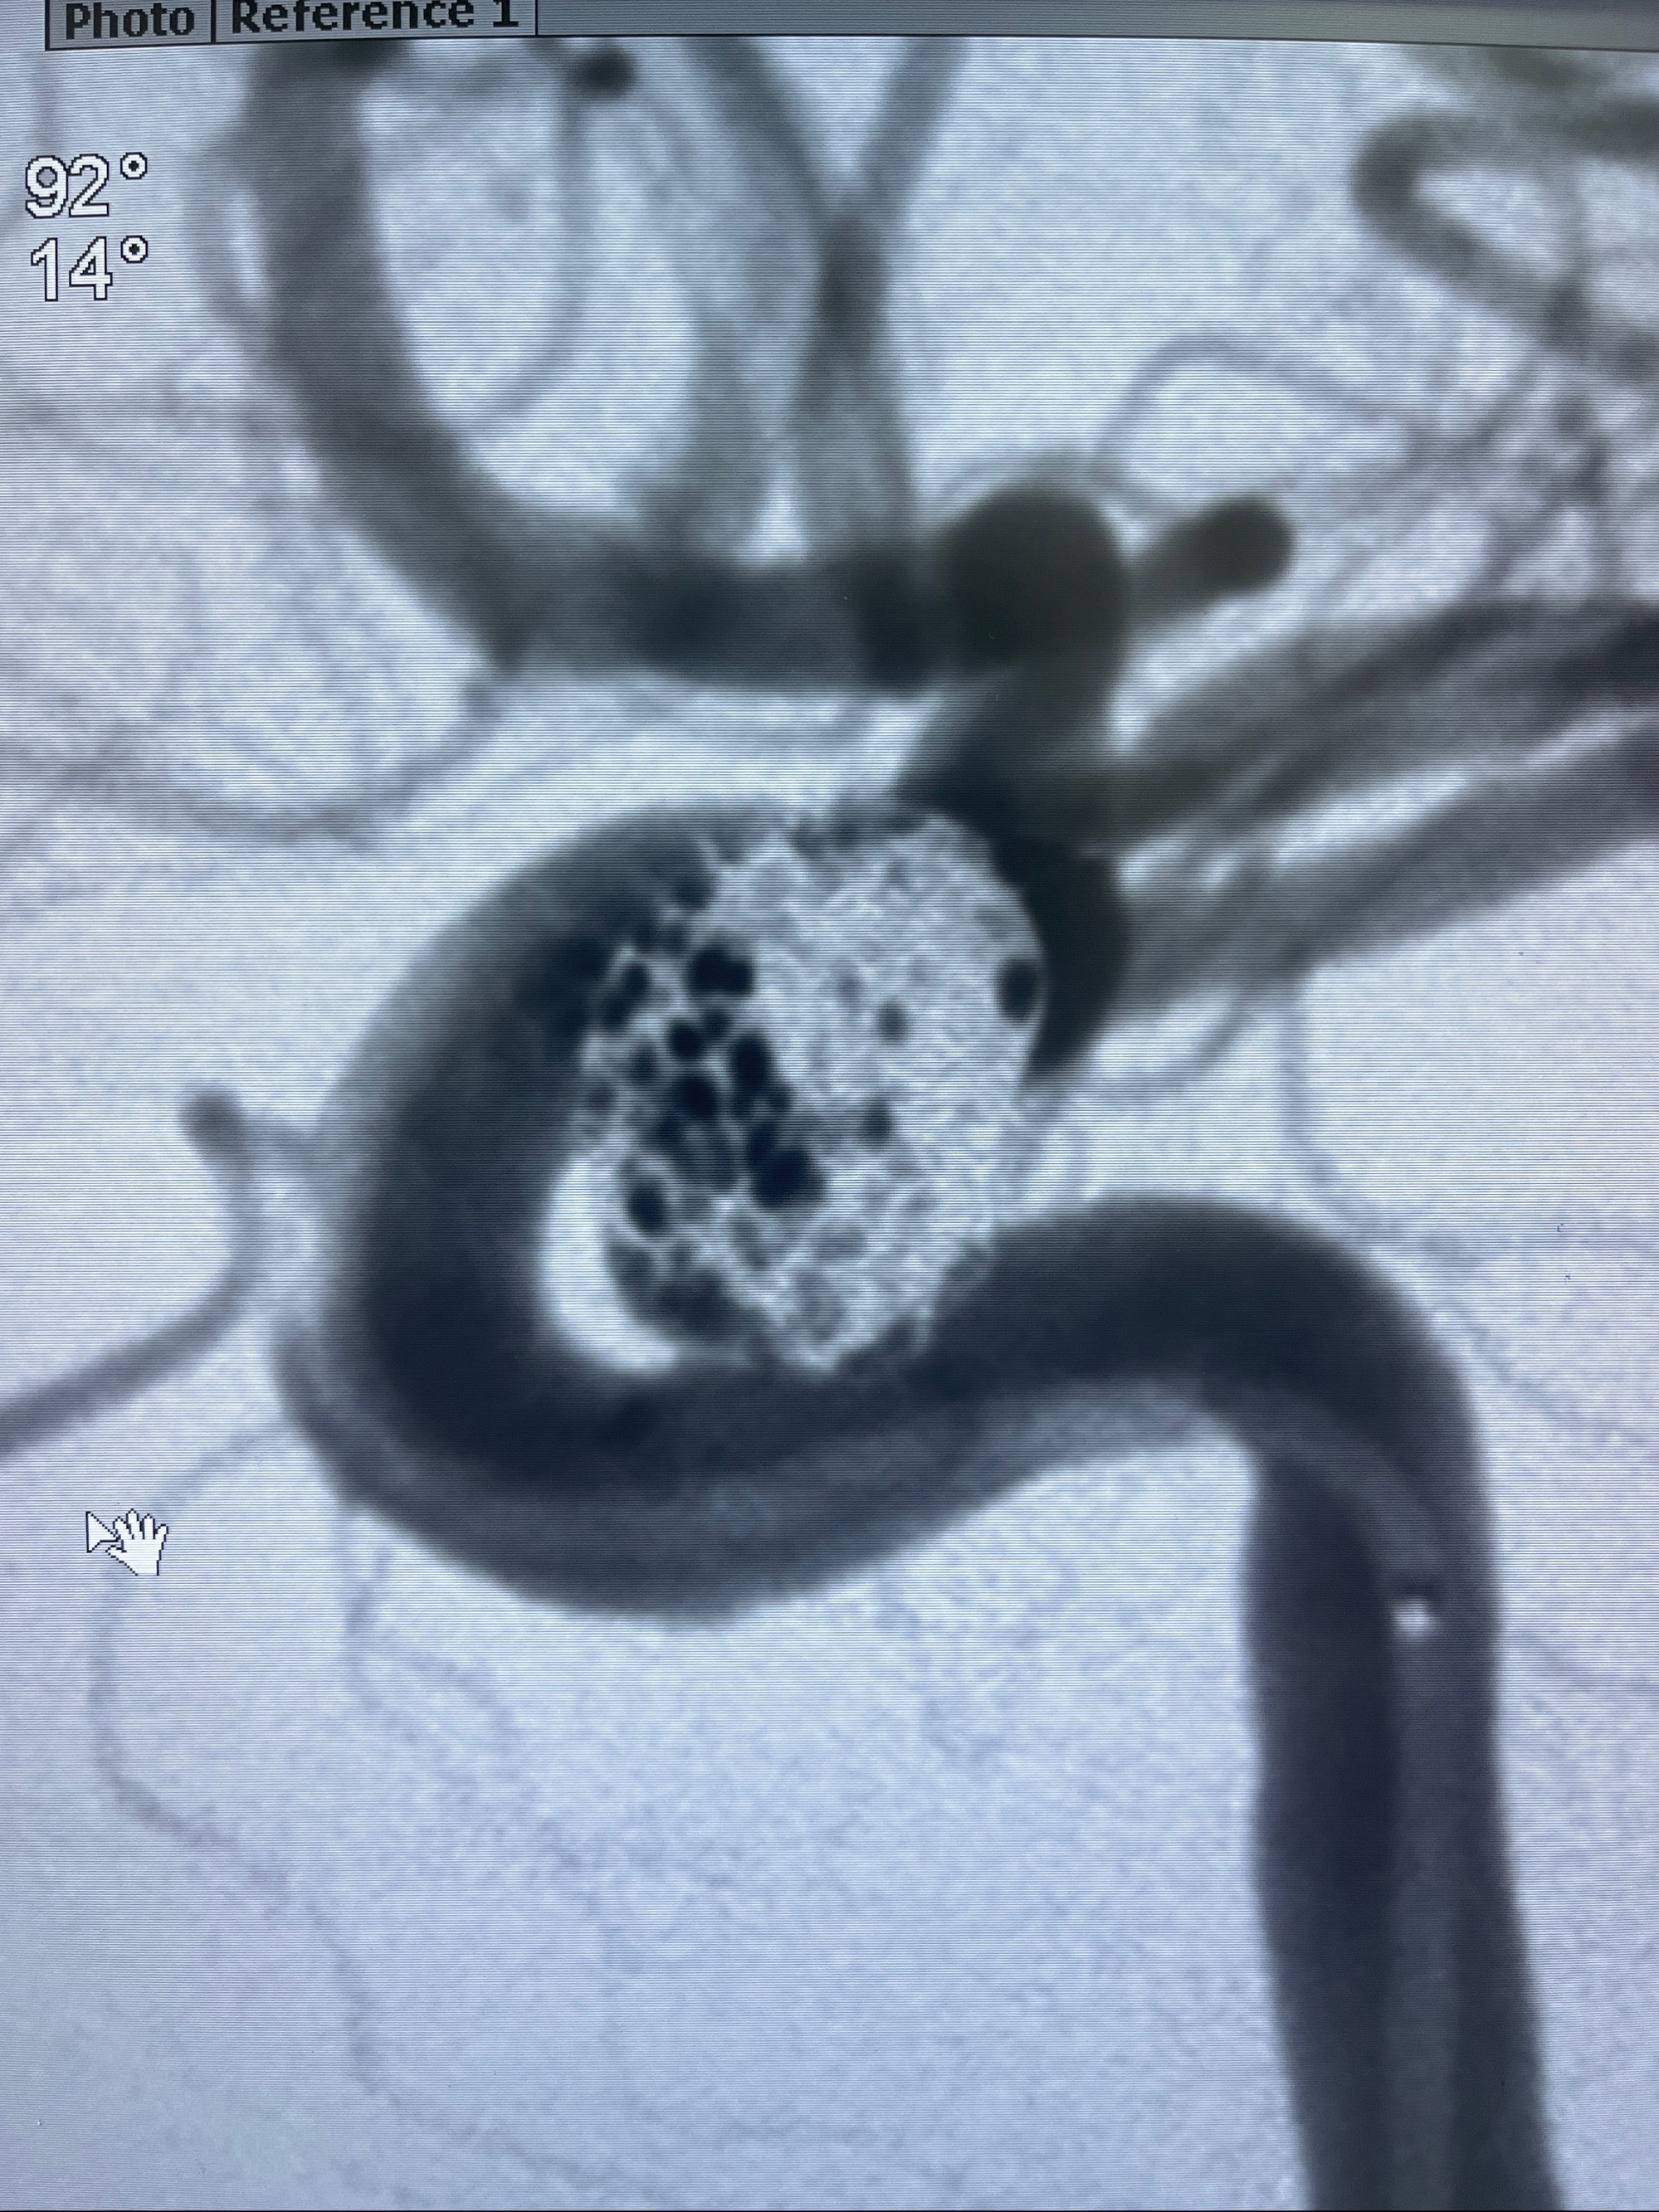

2023-08-30DSA:左侧颈内动脉眼动脉动脉瘤,约3*9.2*7.3mm大小

密网支架辅助栓塞

- Tubridge 4.0-20mm密网支架

- 加奇微弹簧圈:7*30/6*20/5*20/2*8

术后3D显示支架贴壁佳